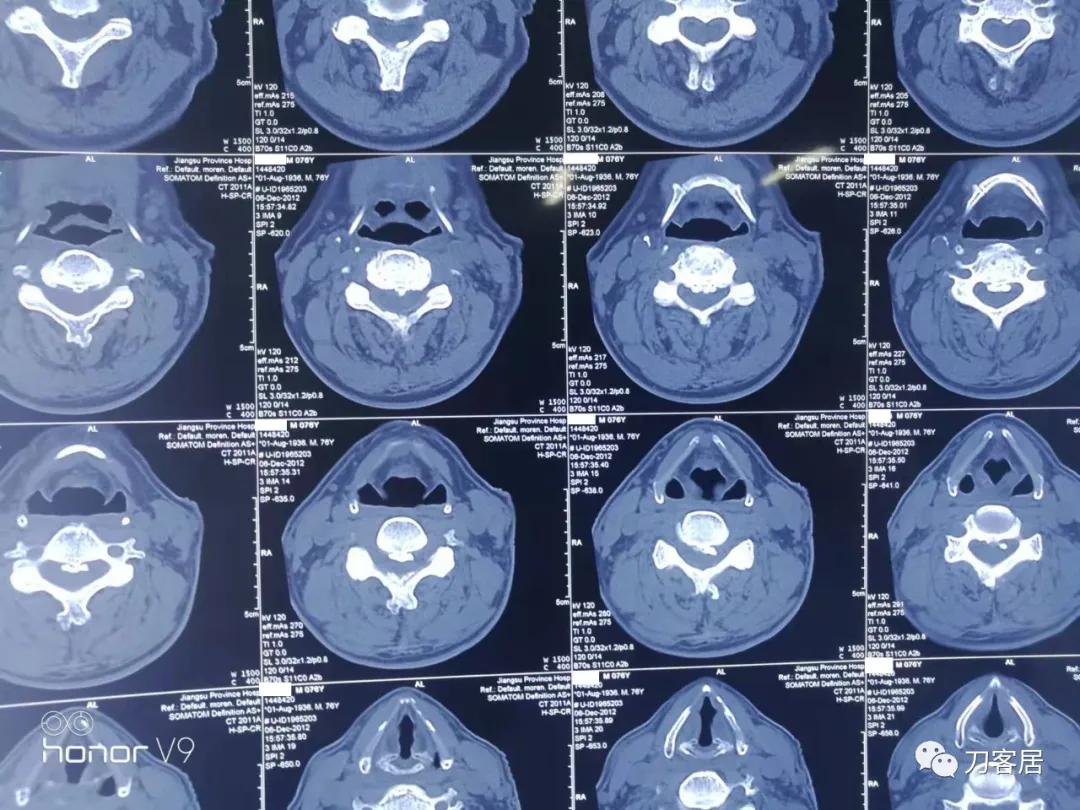

图18. 2012年12月6日颈椎椎管成形术前CT横断面